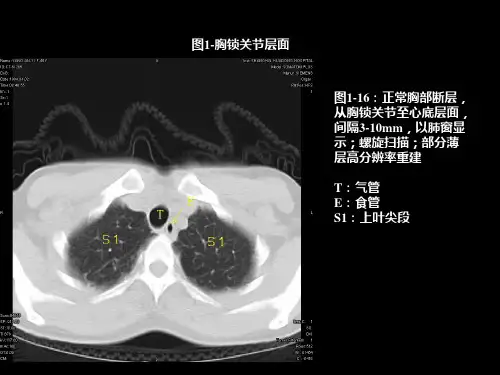

1区:锁骨上淋巴结

下颈部、锁骨上与胸骨颈静脉切迹淋巴 结,自环状软骨下缘至锁骨下缘、胸骨 柄上缘。气管中线是1L与1R的分界线。